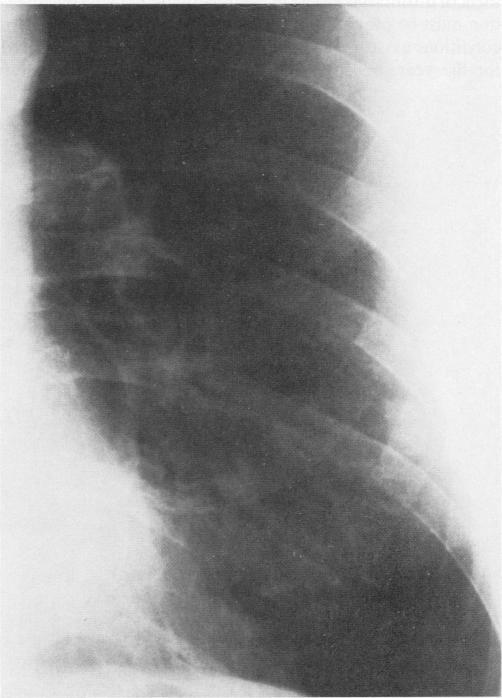

Pulmonary dirofilariasis in humans--pneumonitis that evolved to a lung nodule.

West J Med. 1986 Oct;145(4):516-9.